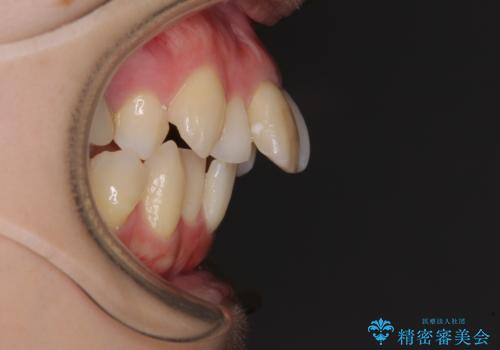

- 口を閉じたときに飛び出してしまう上顎前歯を気にして来院された患者様です。

上下の咬み合わせは上顎歯列全体が歯1本分前にずれている状態であり、さらに上顎歯列はV字型に尖っていたため、上下前歯は全く接触していない状態でした。

上顎左右第一小臼歯を抜去して、ワイヤー装置にて口元の突出感を改善するよう矯正治療を行うこととしました。